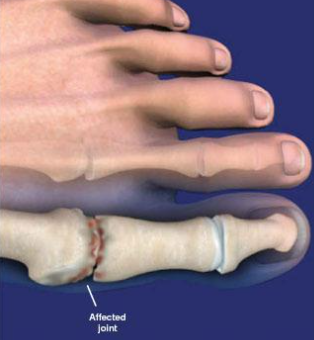

• Caracteriza-se por limitação progressiva na movimentação da 1ª articulação mttf, principalmente em extensão

• Artrose na art. mttf